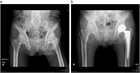

1. CTまたはMRIは有用で診断精度はきわめて高い(推奨度2J)

1. 高齢者の転位型(Garden stage III、stage IV)は人工物置換術を推奨する(推奨度1J)